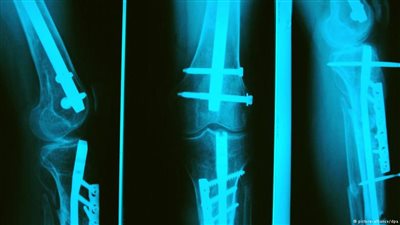

أكد الدكتور خالد عمارة، استشاري طب ورجاحة العظام، أن أدوية منع الحمل لها مضاعفات كثيرة على صحة وسلامة العظام وأجهزة الجسم، مثل الإصابة بالجلطات وأمراض الأوعية الدموية وزيادة الوزن والتأثير على الحالة ...